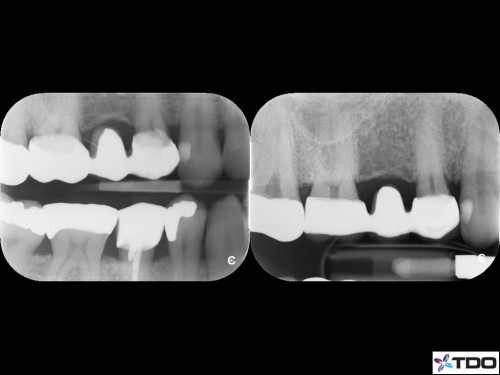

42 yom.

Symptomatic Partially Vital Pulp. No response to cold. Upon access, I observed hyperemic tissue in MB1 and partially vital tissue in the rest of the canals. 2-1-2 MB root system. 1 visit.

Asymptomatic and functional at the follow-up visit.

The treatment was a successful Root Canal Therapy performed in one visit on a tooth suffering from symptomatic Irreversible Pulpitis with complex canal anatomy (MB1 and presumably MB2 were found). nelnet com